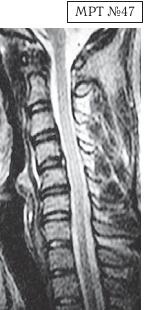

На МРТ № 47 наблюдается сглаженность лордоза с незначительной кифотизацией, которая привела к абсолютному стенозу спинномозгового канала и блоку ликворных путей, а также протрузии в сегменте СIV-СV, вентральному спондилёзу в сегменте CV-CVI и остеофитозу в сегменте CVI-CVII, гипертрофии передней и задней продольных связок.

Это наиболее значительные проблемы в данном отделе.